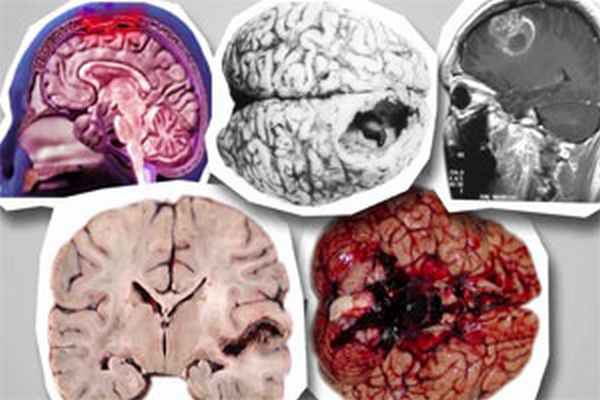

Менингококковая инфекция – это острое инфекционное заболевание, первым признаком которого является острый назофарингит или воспаление носоглотки, протекающее с последующим развитием менингококцемии и гнойного менингита.

И наконец, еще одной тяжелой формой менингококковой инфекции является менингит, который также развивается на фоне острого назофарингита. Менингококковый менингит начинается остро, с подъема температуры тела до высоких цифр, резкой мучительной головной боли, неукротимой рвоты, не связанной с приемом пищи.

Менингококковый менингит

Менингококковый менингит — это бактериальная форма менингита, серьезная инфекция, поражающая оболочку мозга. Он может приводить к тяжелому поражению мозга, а при отсутствии лечения в 75–85% случаев заканчивается смертельным исходом.

Самыми распространенными симптомами являются ригидность затылочных мышц, высокая температура, чувствительность к свету, спутанность сознания, головная боль и рвота. Даже в случае диагностирования и надлежащего лечения на ранних стадиях болезни 5%-10% пациентов умирают, как правило, через 24–48 часов после появления симптомов. При несвоевременно начатом адекватном лечении до 75–85% случаев менингита и менингококцемии заканчивается смертью. У 10%-20% выживших людей бактериальный менингит может приводить к серьезным осложнениям и даже инвалидизации. Осложнения: внутричерепная гипертензия (32,9%), шок (25,8%), отек головного мозга (8,4%), реже инфаркт мозга (2%), потеря слуха или нейросенсорная тугоухость (2,4%), далее это приводит к трудностям в обучении. К сожалению, не редкостью является ампутация пальцев или даже конечностей. Преимущественно данные осложнения отмечаются у детей первого года жизни. Менее распространенной, но еще более тяжелой (часто смертельной) формой менингококковой инфекции является менингококковый сепсис, для которого характерны геморрагическая сыпь и быстро развивающийся циркуляторный коллапс.